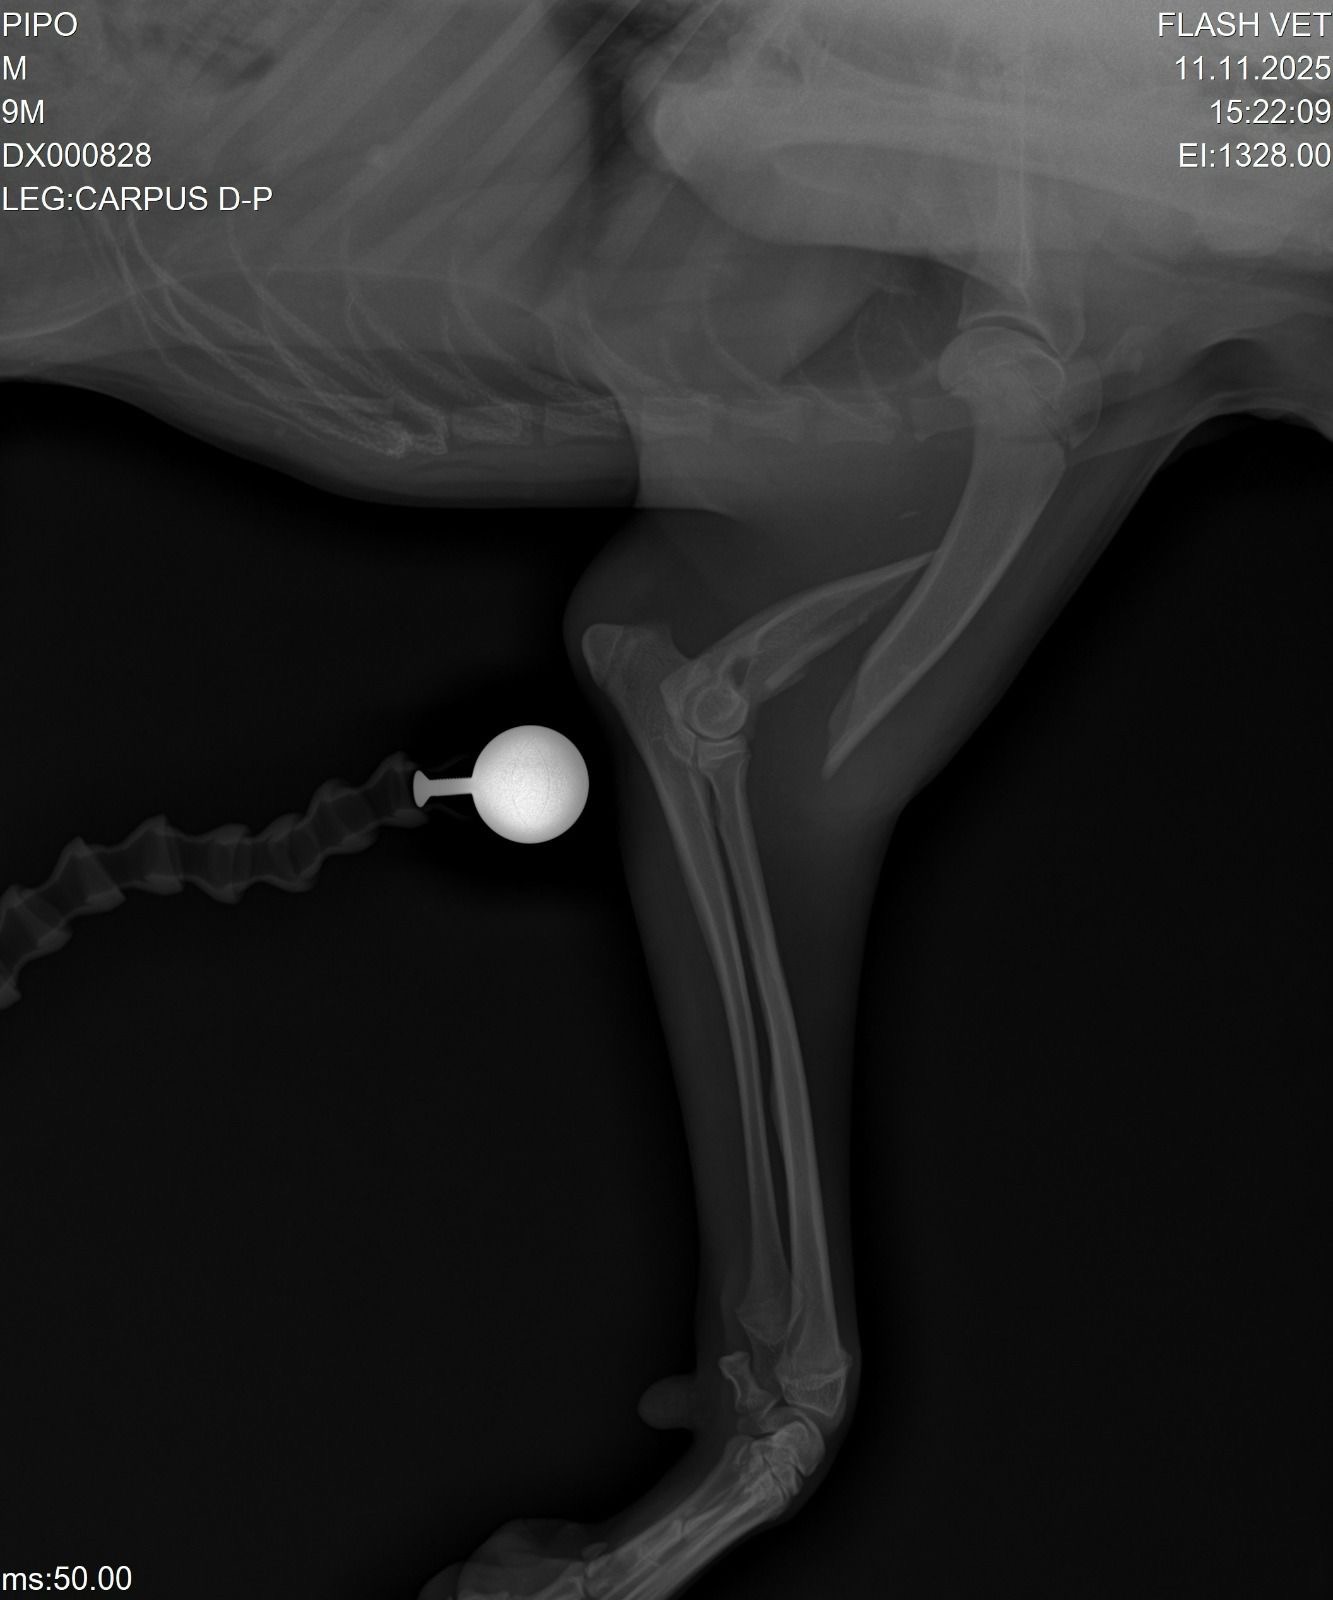

Pipo is a 10-month-old puppy from Brazil who has already faced more than any dog should. He was hit by a car who drove away from the scene, and left him stranded, after being rescued from the street, he was determined homeless with nowhere to go, and was also diagnosed with distemper, a serious viral disease. Unfortunately the area that he currently is, has no shelter anywhere close and he is too sick and in too much pain to travel far at the moment, there is no RSPCA equivalent, and he has no insurance as has no owner.

He’s currently fighting bravely — but one of his front legs is completely fractured, and there’s a possible fracture in his back legs too. He urgently needs surgery, more X-rays, and ongoing treatment to give him a real chance to walk and live without pain.